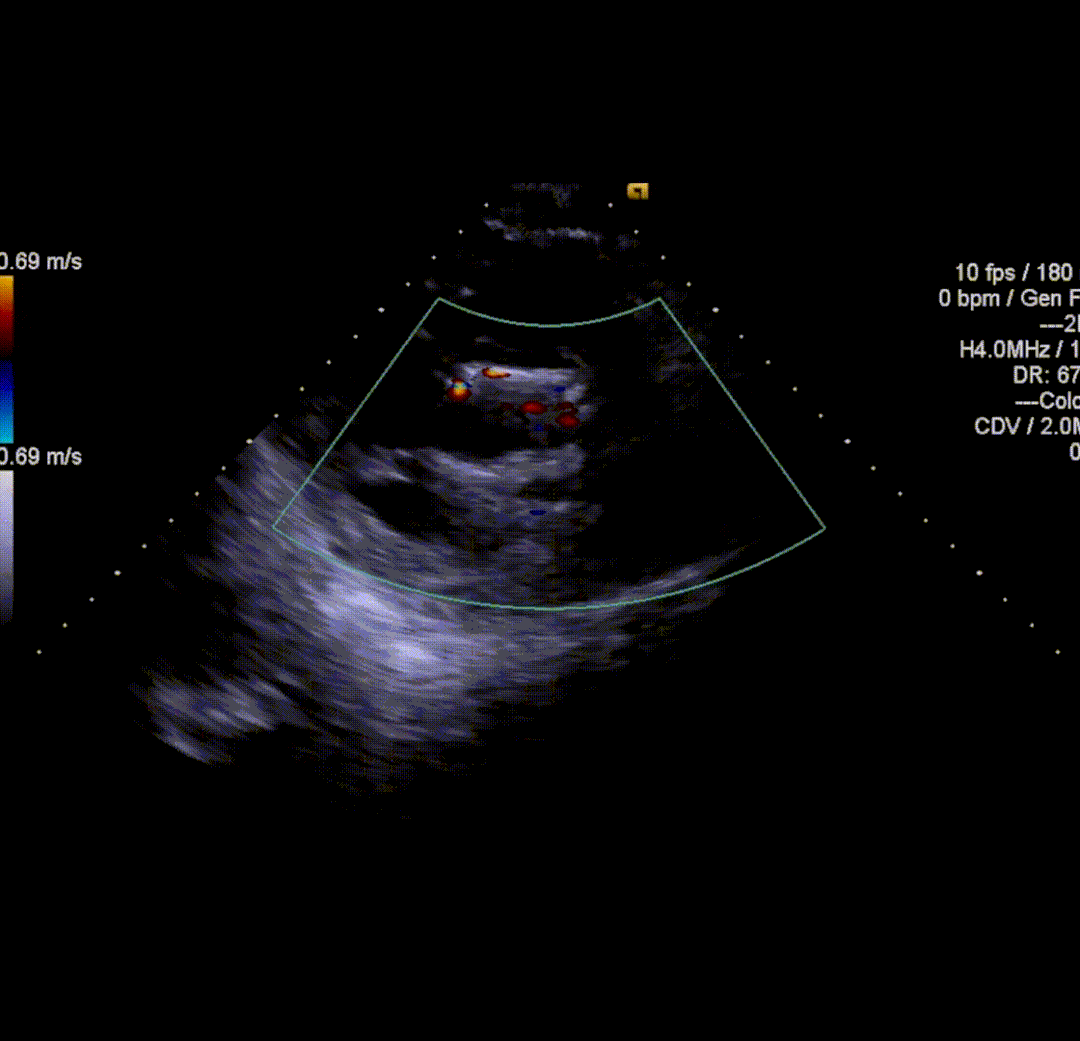

球囊后扩后,瓣膜与周围组织贴合的更好。术后即刻造影结果显示无瓣周漏,工作瓣膜形态优异。术中测量结果显示即刻跨瓣压差降至10mmHg,舒张压从术前35mmHg左右上升到60mmHg以上,术后患者症状明显改善。

术后即刻超声评估